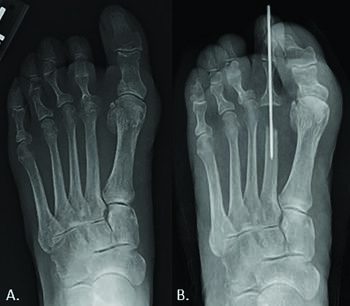

MPJ Arthrodesis. In severe, end-stage joint disease, arthrodesis of the second MPJ provides an alternative treatment option to amputation or isolated metatarsal head resection. Arthrodesis of the second MPJ is a viable option in patients with low ambulatory demands, who suffer from extensive osteonecrosis of the metatarsal head, underwent a failed attempt at a joint salvage procedure, or who have recurrent deformity despite prior intervention. Karlock and colleagues reported clinical outcomes on a series of patients who underwent a second MPJ fusion due to severe crossover deformity. The second MPJ was positioned parallel to the hallux, with a mild dorsiflexed position off the weight-bearing surface, and de-rotated in the frontal plane. The surgeons fixated the arthrodesis with a K-wire and a staple. Ten of 11 patients had clinical and radiographic union, while no patients had recurrence of their deformities. A single patient noted postoperative metatarsalgia despite good arthrodesis alignment.17 Concern for transfer metatarsalgia, stress fractures, and gait abnormalities are also reported, resulting in recommendations to avoid arthrodesis of a lesser MPJ.18 It is common for the senior author to perform adjacent arthrodesis of the first MPJ in younger patients that require second MPJ arthrodesis to shield the lesser MPJ from excessive weight-bearing stress and premature hardware failure (see fourth set of photos above). Although various fixation constructs exist for lesser MPJ fusion, we prefer using a low-profile locking plate contoured to the joint with compression obtained through eccentrically drilled screws within the plate. In the senior authors’ experience, bone allograft is often utilized in conjunction with an arthrodesis.